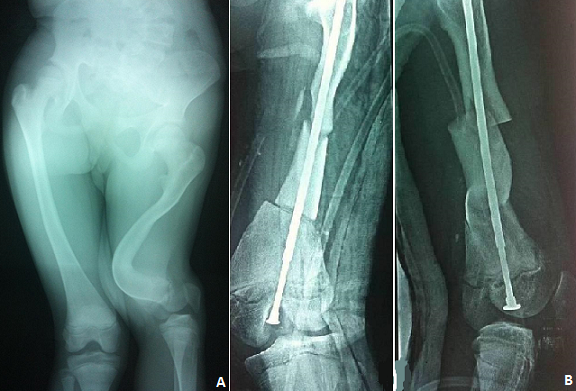

Jeune fille âgée de 14 ans, présentant une déformation de la cuisse droite évoluant depuis l'âge de 2 ans et d'aggravation progressive. L'examen clinique a trouvé des sclérotiques bleus et une déformation de la cuisse droite avec une inégalité de longueur de 5 cm. La radiographie de la cuisse a objectivé une déformation historique du fémur, avec épaississement des corticales et comblement du canal médullaire avec une coxa vara (A). Le diagnostic d'ostéogenèse imparfaite a été retenu et la patiente a bénéficié d'un enclouage télescopique après deux ostéotomiesn (mini abord) (B). L'ostéogenèse imparfaite ou la maladie des os verres ou encore maladie de lobstein est une maladie génétique rare caractérisée par une importante variabilité de l'expression du génotype lié à la grande variabilité des mutations des gènes responsables de la synthèse des deux chaines de collagène type I; il en résulte une fragilité osseuse et une anomalie de la minéralisation de la matrice de l'os. Si le traitement médical basé sur les biphosphonates représente une approche thérapeutique innovante; la prise en charge orthopédique et physiothérapique; dont la fiabilité et l'efficacité ont été établi pour le fémur; reste la base du traitement, car il permet une protection effective et prolongée. Reste à savoir que l'âge est un élément épidémiologique et pronostique important dans la prise en charge, ceci pour éviter l'aggravation des déformations qui va retentir sur la mobilité et la croissance en longueur du membre étant le cas de notre patiente.